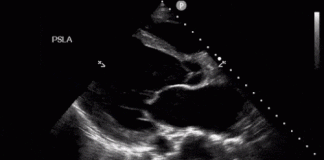

Kritik Hastalarınızın USG ile Değerlendirilmesi (POCUS)

Acil serviste nedeni henüz netleşmemiş şok ya da kritik hastalık tablosundaki hastada ultrason artık lüks değil, temel bir değerlendirme aracıdır. POCUS (yatak başı ultrason),...

RUSH Protokolü Kritik Hasta Değerlendirme

RUSH (Rapid Ultrasound in Shock and Hypotension) protokolü, şok hastasında hızlı etiyolojik değerlendirme amacıyla uygulanır ve temel olarak üç ana bileşeni inceler: “Pump, Tank,...